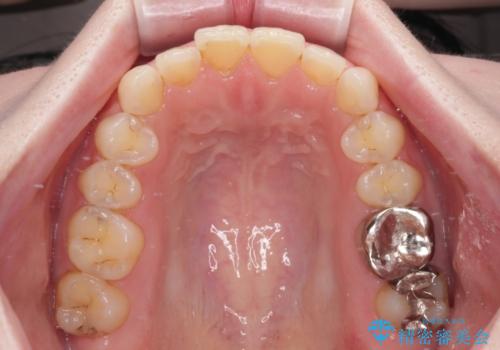

- 奥歯の銀歯をセラミックにしたいとのことで来院された患者様です。

当初は奥歯のみの治療をご希望でしたが、話を進めていくうちに、軽度ではあるものの、幼少期の薬の影響で歯が変色していることがコンプレックスであるということが分かりました。

長年歯の色が塞ぎ込んでいた部分があるとのことで、これを機会に全ての歯を真っ白にするために、オールセラミッククラウンにて補綴治療を行うこととしました。

より白さが目立つように、自然な仕上がりではなく、作り物の雰囲気があるフルジルコニアクラウンにて補綴治療を行いました。